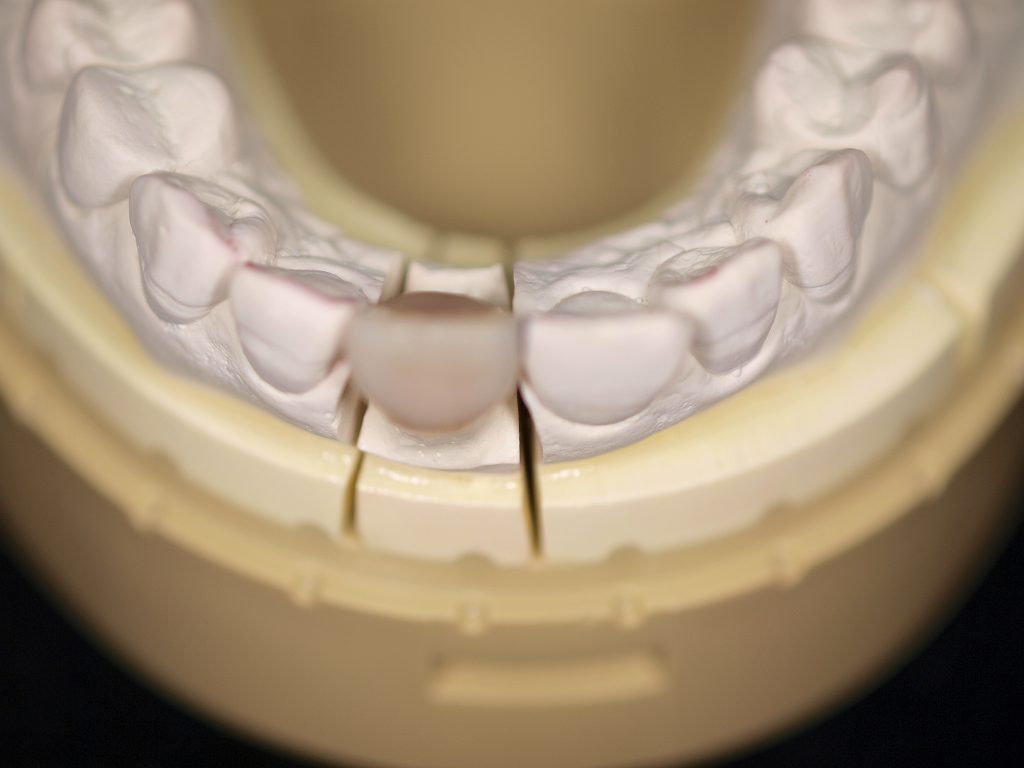

完成したオールセラミックになります

このように完成しました

きれいな歯に塩上がっていますが、、

口腔内にて歯冠の幅径が広くならざるを得なく、咬合の

影響を受けてこのような形態に仕上がっています

理想的な歯に仕上げるには下前歯の咬合調整、左上2番の近心部に

CRなどで歯冠幅径を狭くする工夫が必要かもしれませんが、

歯をけずる行為もCR充填にも限界があります